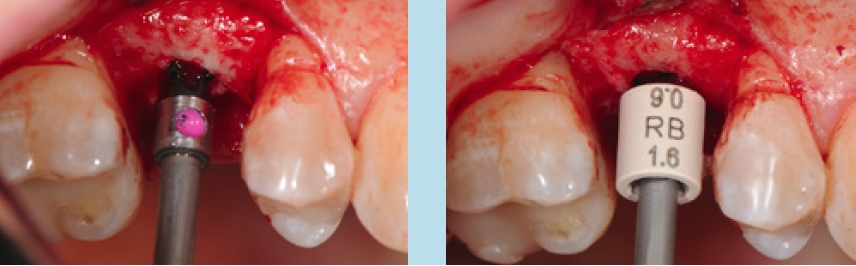

In diesem Fall konnten 2 NobelPearl-Implantate mit je einem Durchmesser von 4,2 mm und der Länge 10 mm für die Implantatpositionen 15 und 25 vorgesehen werden. Die angegebene Länge entspricht dabei dem enossalen Anteil des Implantats. Zu beachten ist, dass zum enossalen Anteil noch ein auslaufend geätzter Halsbereich mit 1,6 mm Höhe hinzukommt, welcher der biologischen Breite Rechnung tragen soll. Folglich weist ein 10-mm-Implantat eine Gesamtlänge von 11,6 mm auf. Die untere Schulter des Profilbohrers entspricht hierbei der enossalen Länge des Implantats ohne den Halsbereich (Abb. 4). Bei einer geringen Mukosadicke kann das Implantat jedoch bis zu 1 mm tiefer platziert werden, sodass nur noch ein Halsbereich von 0,6 mm suprakrestal verbleibt und der enossale Anteil nun 11 mm beträgt.

Unter Lokalanästhesie erfolgte nach krestaler Schnittführung die Aufklappung (Abb. 5) und die Aufbereitung des Implantatbettes gemäß dem chirurgischen Protokoll für NobelPearl mit den Bohrern des NobelPearl Surgical Tray. Nach Ankörnung mit dem Rosenbohrer wurde unter Beachtung der korrekten Implantatachse die 1. Bohrung mit dem zylindrischen Pilotbohrer Ø 2,3 mm auf die geplante Länge von 10 mm angelegt. Für die unterschiedlichen Längen stehen in der Folge formkongruente Profilbohrer zu Verfügung. So wird für die weitere Aufbereitung zunächst der Profilbohrer „small“, Länge 10 mm, Ø 3,3 mm (Farbcodierung violett), und danach der Profilbohrer „regular“, Länge 10 mm, Ø 4,2 mm (Farbcodierung gelb, hier mit Tiefenstopp), ausgewählt (Abb. 6).Da das NobelPearl-Implantat nicht selbstschneidend ist und beim Eindrehen des Implantats der Werkstoff Keramik keine Temperatur wie ein Titanimplantat ableitet, muss als letztes Instrument der Gewindeschneider auf die gesamte Implantatlänge eingesetzt werden.